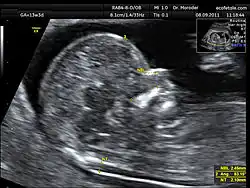

La translucencia nucal consiste en la medición de un espacio sonoluscente o econegativo situado en la zona posterior de la nuca del feto. El momento adecuado para realizar esta medición es la semana 12 aunque puede realizarse entre las semanas 11 y 14 del embarazo.

Para realizarse correctamente el calliper o cursor ecográfico se debe posicionar en las partes internas de los ecos que definen la sonoluscencia. La ecografía debe realizarse vía abdominal aunque pueden obtenerse las imágenes también vía vaginal.